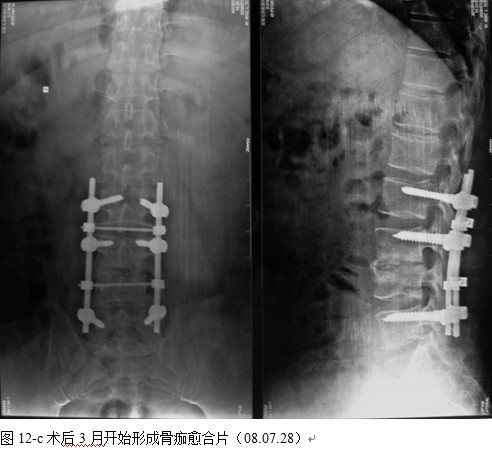

结果: 术后所有患者均显示,骨性融合, 马尾神经损伤的患者均基本恢复正常,术后后凸畸形平均矫正90%以上, 3-49个月的随访,后凸角度平均丢失4.2°。

本组手术用时间3~4h , 平均3.5h 。术中出血300~500ml , 平均约350ml 。术后症状完全缓解,无神经功能障碍加重等并发症,1例营养差的老年患者伤口出现窦道,1例因肝功能差,术后未口服抗痨药,伤口出现窦道,经换药后二期愈合,其余病例伤口均一期愈合。马尾神经受损的患者术后基本恢复正常。术后一周后凸角平均 5.4°后凸畸形平均矫正90%以上, 最终后凸角平均8.3°,后凸角度平均丢失4.2°。随访3个月有87%(40/46)有骨痂形成,6个月91.3%(42/46)明显骨性愈合(见图),其余4例9-12个月内愈合,随访时间3-32个月,平均11个月,46例患者中2例在术后2个月和3个月时背部形成脓肿,换药后治愈。2例出院1月后并发结核性脑膜炎,治疗后好转。1例因椎弓根钉偏外,刺激神经根,5个月后从侧方脱出,疼痛加重,因前后路植骨完全愈合,取出后症状完全缓解。